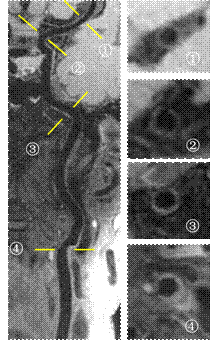

脑动脉和颈动脉血管壁联合成像。左侧图像为曲面后重建图像显示颈总动脉、颈内动脉和脑动脉血管壁全景。右侧为不同部位(①~④)的横断面图像显示颈内动脉近分叉处斑块形成以及③附近的早期动脉粥样硬化病变(血管壁增厚)。空间分辨率0.6 mm各向同性,扫描时间8分钟。